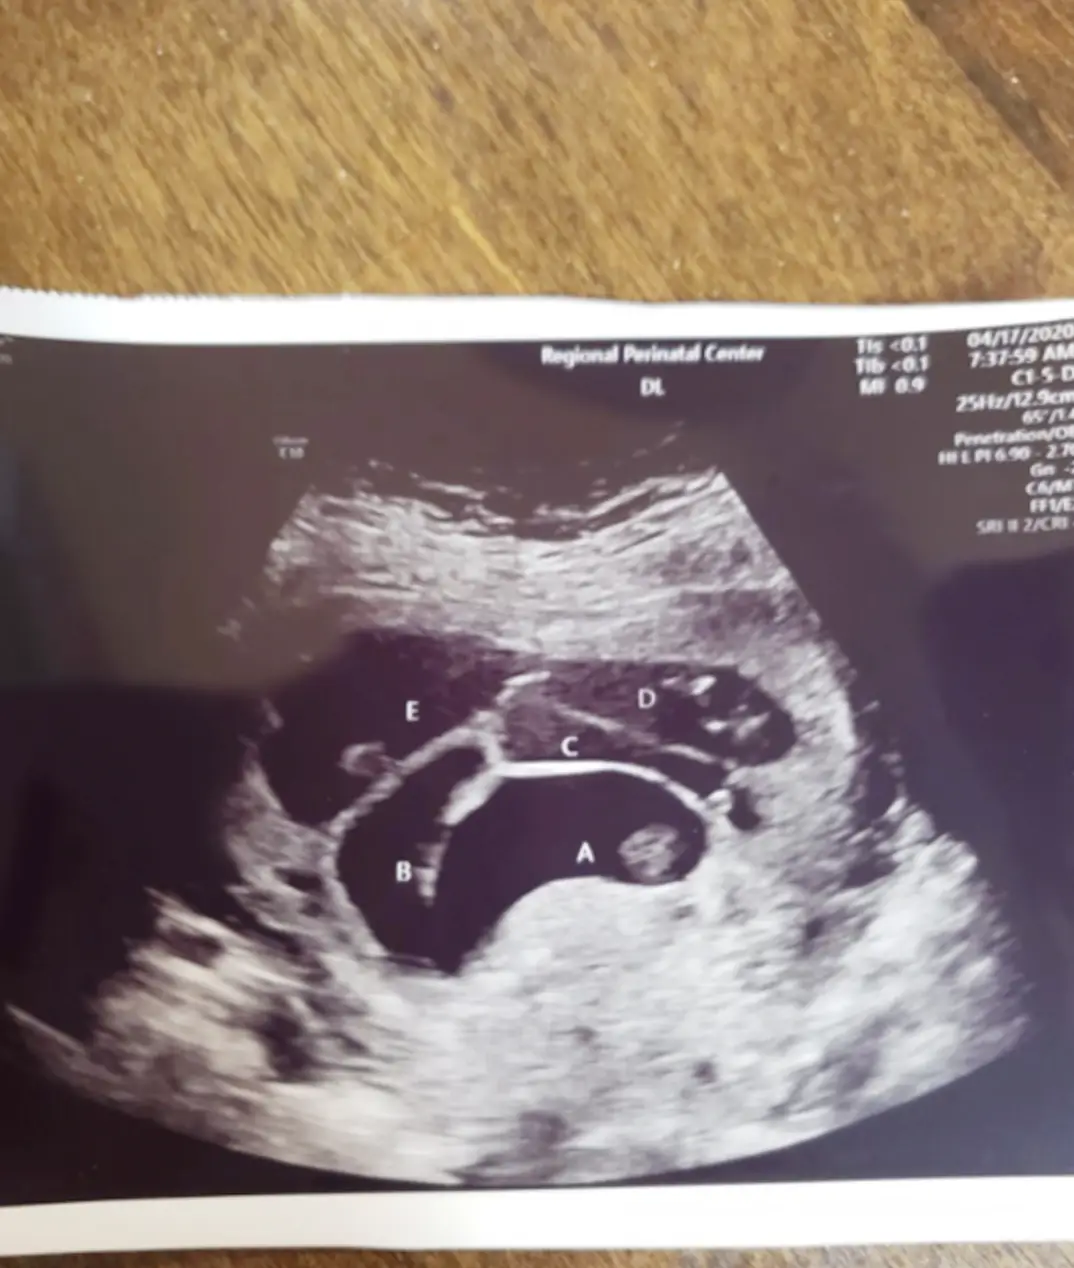

The birth of Hadley, Reagan, Zariah, Zylah and Jocelyn was so ʀᴀʀᴇ that they are just the second set of ʀᴇᴄᴏʀᴅᴇᴅ ᴀʟʟ ɢɪʀʟ ǫᴜɪɴᴛᴜᴘʟᴇᴛs ɪɴ ᴛʜᴇ US. The couple, who have been together for nine years, already had a daughter together, Sawyer, three. They decided they wanted to try for one more baby, however, ended up with five more. Heather says that she was just six weeks pregnant when they discovered they were having ǫᴜɪɴᴛᴜᴘʟᴇᴛs.

She added: “Initially doctors only saw four ɢᴇsᴛᴀᴛɪᴏɴᴀʟ sᴀᴄs, but then they found the fifth one. I immediately felt sᴄᴀʀᴇᴅ when we found out there was going to be five because I feared my pregnancy would be worrying and complicated.